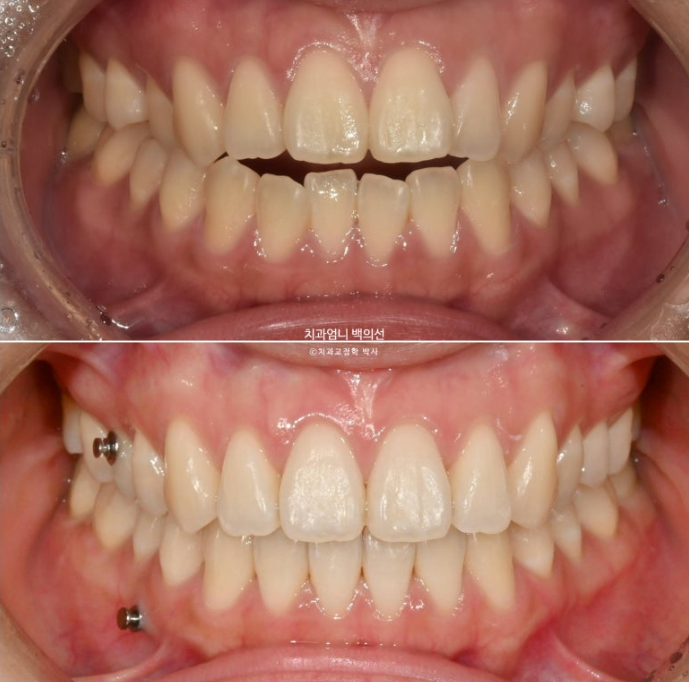

25년 4월 치료를 마무리 했습니다. 중심선은 이제 정확히 맞습니다.

철사유지장치 부착 후 환자분은 가철식 유지장치로 비베라를 선택했는데 비베라 제작을 기다리는 2주동안 사진상 메탈고리와 하악 미니스크류 사이에 고무줄을 걸면서 초진시 떠있던 해당치아의 교합을 유지합니다.

처음에 들려있던 치아라 철사유지장치 부착 후 아무 장치도 안 끼기 시작하면 재발에 의해 미세하게 다시 들리기 때문입니다.

어금니 교합은 좋습니다.

이제 전 후 비교 보겠습니다.

배열은 좋으며 철사유지장치까지 붙은 모습입니다.

23.11~25.04